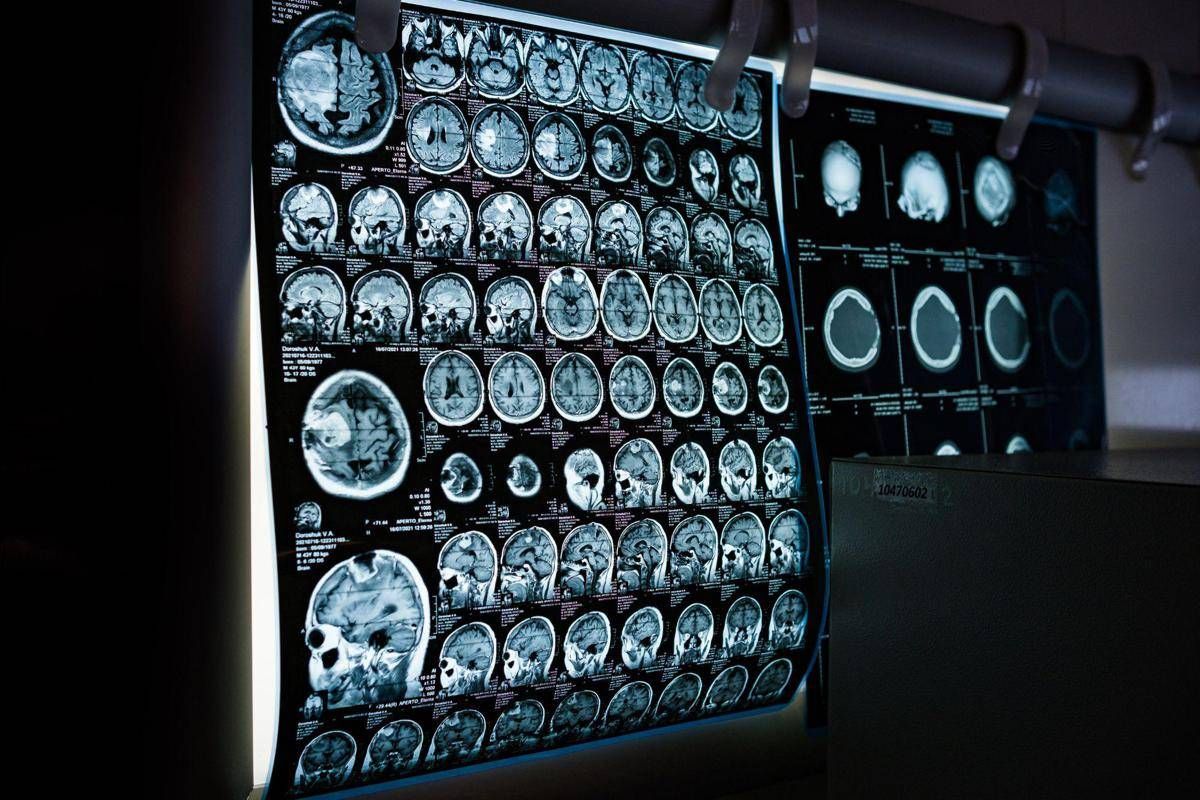

(Adnkronos) - Uno spray nasale testato sui modelli animali potrebbe invertire l'invecchiamento del cervello con sole 2 dosi, riducendo drasticamente l'infiammazione cerebrale, ripristinando le centrali energetiche cellulari del cervello e migliorando così significativamente la memoria. Un processo di ringiovanimento che agirebbe nel giro di poche settimane per durare mesi.

E' il risultato dello studio condotto dai ricercatori della Texas A&M University (Naresh K. Vashisht College of Medicine) negli Stati Uniti. Lo spray contiene minuscole particelle biologiche note come vescicole extracellulari (Ev), che agiscono come veicoli di consegna con a bordo un potente carico genetico, i microRna. Le sostanze aggirano lo scudo protettivo del cervello e viaggiano direttamente nel tessuto cerebrale, dove vengono assorbite. Arrivati a destinazione nelle cellule immunitarie residenti nel cervello, i microRna 'spengono' i sistemi noti per essere responsabili dell'infiammazione cronica nel cervello che invecchia.

Per spiegare il senso di questo processo, gli scienziati invitano a immaginare il cervello come un motore ad alte prestazioni: nel corso dei decenni questo motore non solo si usura, ma inizia anche a surriscaldarsi. Piccoli 'focolai' di infiammazione covano nelle profondità del centro della memoria, creando una persistente nebbia mentale (brain fog) che rende più difficile pensare, formare nuovi ricordi o persino adattarsi a nuovi ambienti, aumentando al contempo il rischio di disturbi come il morbo di Alzheimer. Questo processo a lenta combustione viene chiamato neuroinfiammazione. E per decenni si è pensato che fosse il prezzo inevitabile dell'invecchiamento. Ma il nuovo studio, pubblicato sul 'Journal of Extracellular Vesicles', suggerisce che l'ondata infiammatoria potrebbe essere reversibile.